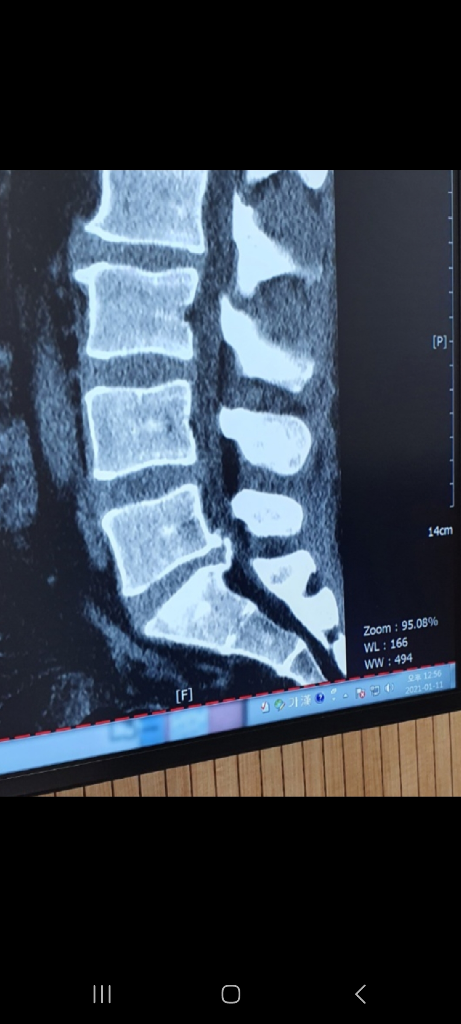

경추 후종인대 골화증 ct mri 사진좀 봐주세요...

33세 남성입니다 1월 11일부터 팔이따갑다 안따갑다합니다 힘빠지는 증상은 없으며 간혹 목뒤도 아픕니다

담당 신경외과 전문의 선생님께서 아주좋지도않고 아주 나쁘지도않은 상황이니 지켜보자 하시는데 다른 선생님 분들이 보셨을때는 어떤가요 ?

척수병증이 MRI에서 보일려면 척수에 병변이 있어야 합니다, 그러니까 색이 변해야 하는거죠

현재는 그런 양상은 보이지 않고 표시한 부분에서 압박하는 양상만 보입니다

신경외과 교수님 말씀에 동의합니다